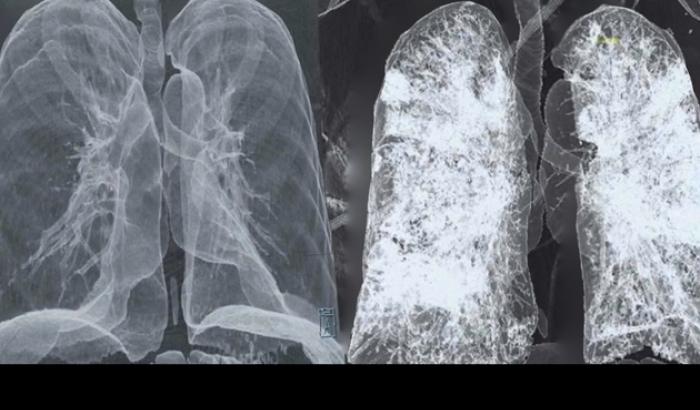

A scatenare i tumori del polmone in chi non ha mai fumato sono mutazioni diverse da quelle che entrano in azione nei fumatori: la scoperta, frutto di una ricerca internazionale pubblicata sulla rivista Nature Genetics, segna un importante passo in avanti verso terapie personalizzate per le diverse forme di tumore dei polmoni e ha permesso di individuare, nei non fumatori, almeno tre tipi di mutazioni legate ad altrettanti sottotipi di tumore dei polmoni.

Landi e il suo gruppo di lavoro hanno ottenuto la sequenza del Dna di tumori prelevati da 232 pazienti che non avevano mai fumato e malati di tumore del polmone; per il 75% erano donne e l’età media era di circa 65 anni. “Quello che stiamo vedendo è che ci sono diversi sottotipi di cancro ai polmoni nei non fumatori che hanno caratteristiche molecolari e processi evolutivi distinti”, osserva Landi.